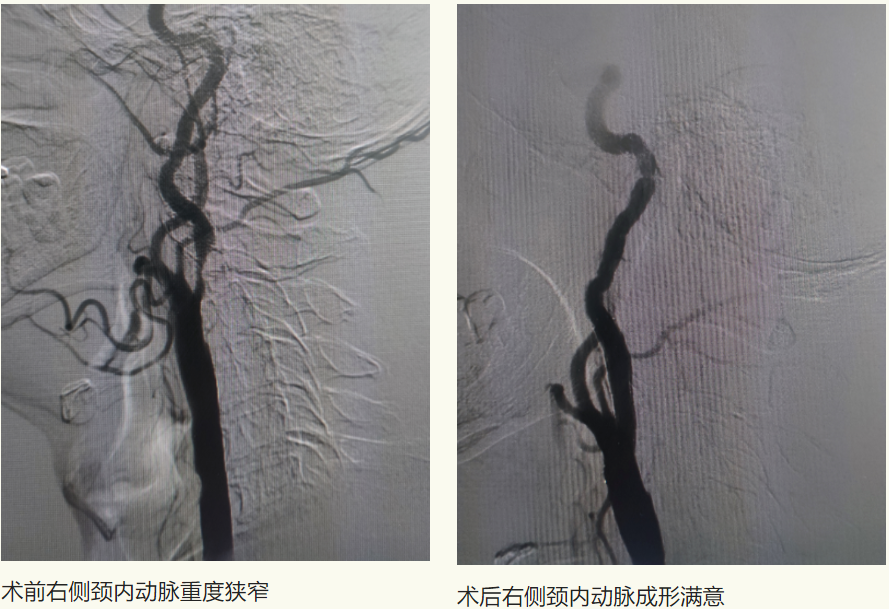

6月10日,家住富区74岁的李先生因“头晕伴行走不稳多年”,来到齐医附属一院就诊。行头CTA检查提示左侧锁骨下动脉管腔重度狭窄、双侧颈内动脉颅内段钙化斑块、管腔轻-中度狭窄、左侧大脑前动脉A1段重度狭窄。患者饱受疾病折磨,长年头晕给生活带来诸多不便,生活质量下降。以往此类患者需前往哈尔滨或者北京等著名医院进行介入手术治疗,大大增加了患者就医困难及经济负担。李先生经多方咨询,了解到刘忠锦副院长为神经介入专家,找到了附属一院刘忠锦副院长来完成治疗。

刘忠锦副院长经过仔细的问诊、查体后和家属详细的进行了沟通,患者选择相信附属一院的技术,决定住院进行手术治疗。入院后刘忠锦副院长带领神经介入团队及神经内五科医生认真地查房及阅片,经全脑血管造影诊断为左侧锁骨下动脉重度狭窄、锁骨下动脉盗血综合征,并制定了手术方案。

6月12日,经过完善的术前准备后,刘忠锦副院长带领神经介入团队为患者行锁骨下动脉支架植入术,术后支架形态良好,前向血流恢复,左侧椎动脉血流较手术前明显改善,且无并发症发生。